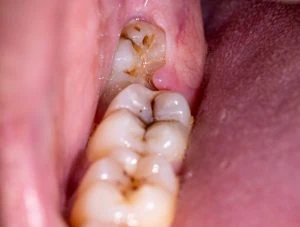

Sometimes, wisdom teeth come only partially and leave some gum tissue over the top. If food and bacteria get trapped under this flap of gum, it can create a suitable environment for cavities to form. You may also find it harder to clean partially erupted wisdom teeth because it is hard for the toothbrush to clean under the gum tissue.

The Tooth Is Partially Erupted or Impacted

If your wisdom teeth are only partially erupted or trapped under the gum, they are more likely to get repeated decay and infection. In these cases, dentists recommend extracting them rather than fixing them.